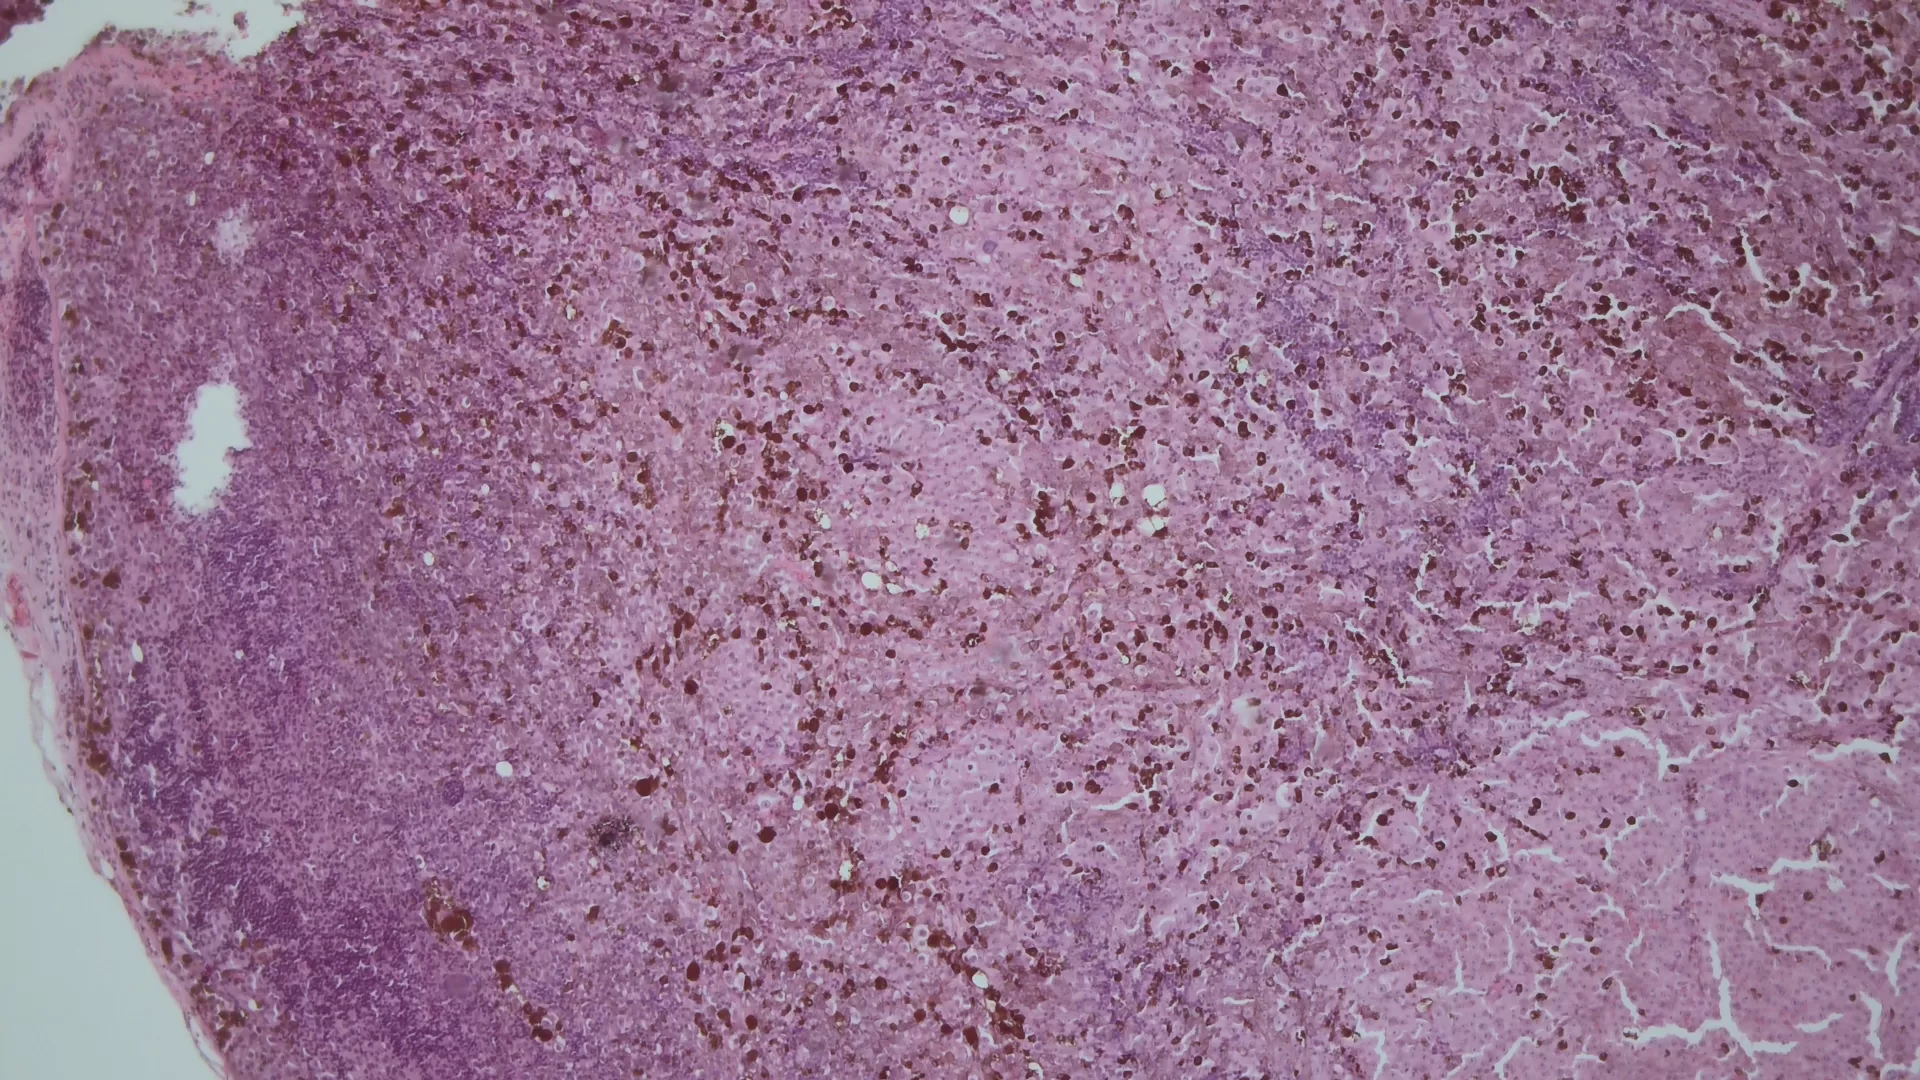

12-кишка: Просвет луковицы двенадцатиперстной кишки обычный, содержит небольшое количество желчи, перистальтика активная , слизистая оболочка розового цвета, ворсинки сохранены. Так же прослеживаются пигментированные образования от 2мм до 8мм. серо-синюшного оттенка. Постбульбарном отделе множественные пигментые образования до 10мм, единичные кратообразные пигментные образования до 15мм, глубиной до 5мм., дно покрыто серым фибрином. Биопсия 2-а кусочка.

Заключение: ГПОД. Грыжевая гастропатия. Эрозивная гастропатия антрального отдела желудка. MTS Меланома ЛДПК, залуковичного отдела. Биопсия.

В Январе 2024: выполнено иссечение правого пахового л/узла с последующей гистологией.

Гистологическое заключение : Метастаз пигментной меланомы в лимфатическои узле.